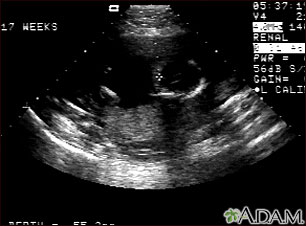

An ultrasound during pregnancy is done to confirm the diagnosis. The ultrasound may reveal too much fluid in the uterus. This condition is called polyhydramnios.